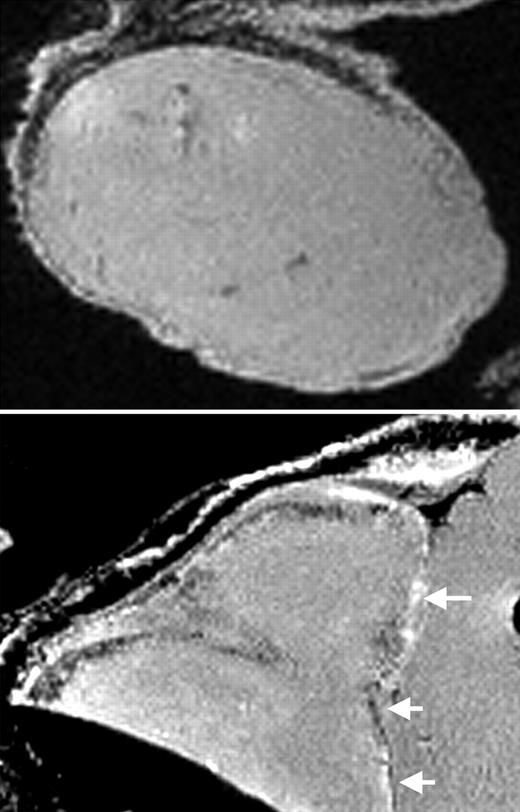

Writing in this issue of Blood, Arbab and colleagues strongly suggest an affirmative answer to the latter question in their use of a combination of FDA-approved agents to label several human and murine cell types. The authors use the commonly used transfection agent protamine sulfate to modify a commercially available suspension of dextran-coated SPIOs known as ferumoxides. Protamine sulfate is FDA approved for the treatment of heparin overdoses, while ferumoxides have been FDA approved for use as an MR contrast agent in the diagnosis of liver cancer for more than 7 years in the form of Feridex IV (Berlex Laboratories, Wayne, NJ). The article establishes that the combination of these agents results in an effective preparation of magnetically labeled cells. In the article, the authors initially define ferumoxide–protamine sulfate ratios that provide optimal relaxation properties for contrast enhancement, and proceed to demonstrate that this combination permits extremely high labeling efficiency as well as minimal short- and long-term effects on cellular toxicity, proliferation, and differentiation in the examined cell types. In so doing, this research identifies a promising magnetic cell-labeling strategy that is appropriate for potential clinical development and delineates a paradigm for the evaluation of such strategies prior to clinical implementation. This group has pioneered the use of transfection agents in combination with SPIOs for cell labeling and MR-based cell tracking.4 The authors' progress in this area affords an example of the systematic development of bench research for bedside application. The work of Arbab et al represents an important step in this effort, suggesting the prospective design of future clinical trials.FIG1

MRI of labeled CD34+ cells in tumors. See the complete figure in the article beginning on page 1217.